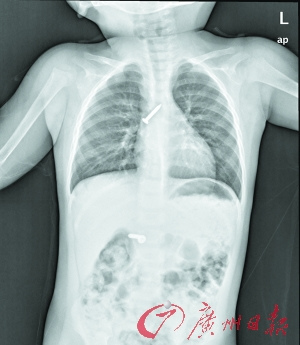

“当时捏开花花的嘴,但已看不到钢钉了。料想钉子已经掉进肚子,会划破内脏……”女童的爷爷说,他赶紧带着花花到高州市人民医院胸外科就医。X光片检查显示,两枚钢钉竟然卡在了气管和小肠里。

医院胸外科、耳鼻喉外科、小儿胃肠外科的专家们紧急联合会诊后,又忧又“喜”。忧的是,气管内卡住的钉子很容易引起刺激咳嗽,发生挤压钉子活动,那么尖锐的钉子就可能刺破气管及其毗邻的颈内大血管,导致大出血而直接危及生命,必须予以及时手术取出。“喜”的是,跑入小肠的钢钉短平而不尖锐,刺破肠管的可能性较小,一时不会带来生命危险,可让其自行排出。

耳鼻喉外科的两位医生为花花施行支气管镜异物取出术。但是气管内的钢钉尖端向上,钉体光滑,加上气道黏液作用,几番钳取都遭滑落,医生反复努力才取出了该钉。而肠道内的另一枚钢钉,在胸外科专家的观察下实施保守治疗,于两天后随着排便排出体外。